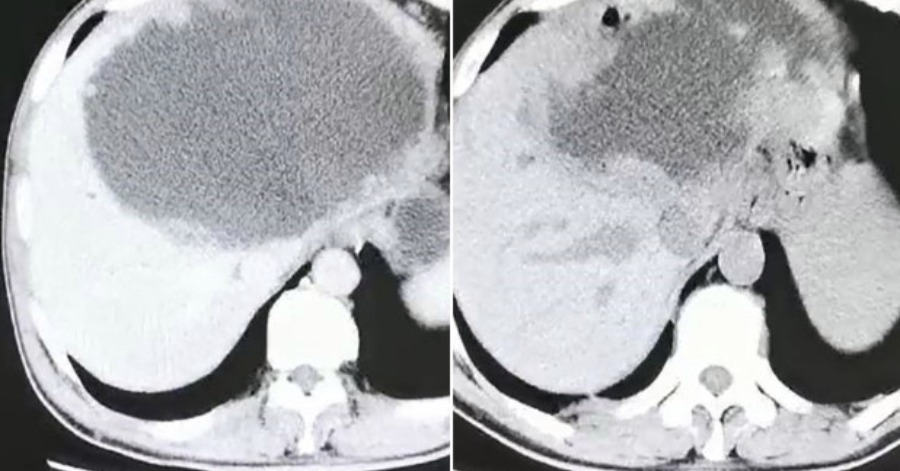

Hati Lelaki Ini Jadi ‘Sarang’ Telur Cacing Selepas Makan Ikan Mentah

Seorang penduduk yang malang di China terpaksa mengeluarkan separuh hatinya setelah dipenuhi telur cacing akibat makan ikan mentah. Menurut laporan akhbar dari Hangzhou First People’s Hospital di timur China penduduk Hangzhou yang berusia 55 tahun itu, telah mengalami kehilangan selera makan, keletihan dan sakit perut setelah mengunjungi keluarganya di Sichuan pada bulan Februari lalu. Bagaimanapun, […]